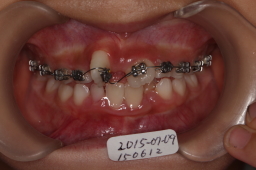

2015年07月09日

上顎にワイヤーを入れて曲がった歯を直しています。

歯が少しまわっているのがわかると思います。